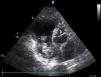

Na gasometria foi identificada uma alcalose respiratória grave. O ECG demonstrou ritmo sinusal, com bloqueio bifascicular. Analiticamente, de relevante, apresentava elevação da troponina i, D-dímeros e do BNP. No ecocardiograma identificou-se dilatação grave das cavidades direitas, depressão da função sistólica do ventrículo direito (TAPSE 11mm) e múltiplas formações cilíndricas no interior aurícula direita, sugestivas de trombos. (Figuras 1 e 2) A insuficiência tricúspide era ligeira e a pressão sistólica arterial pulmonar de 45mmHg. Perante estes achados, considerou-se desnecessária a realização de exames complementares adicionais e assumiu-se o diagnóstico de tromboembolia pulmonar (TEP) de risco elevado. Iniciou-se de imediato anticoagulação com heparina e suporte aminérgico com dopamina. Atendendo ao limitado status funcional da doente e à ocorrência de um AVC isquémico recente, optou-se pela não realização de fibrinólise ou embolectomia. A doente veio a falecer 2 depois.

A identificação no ecocardiograma transtorácico de trombos nas cavidades direitas, no contexto de TEP, é um achado pouco frequente (4 a 18%)1,2. Nas TEP de risco elevado, esse achado é mais comum e é um comprovado fator de mau prognóstico3,4. Nestes casos, o tratamento deve ser iniciado precocemente (fibrinólise e/ou embolectomia), seguido de anticoagulação efetiva com heparina. A anticoagulação isolada demonstrou ser ineficaz. Na ausência de terapêutica, a taxa de mortalidade atinge os 80-100%5.